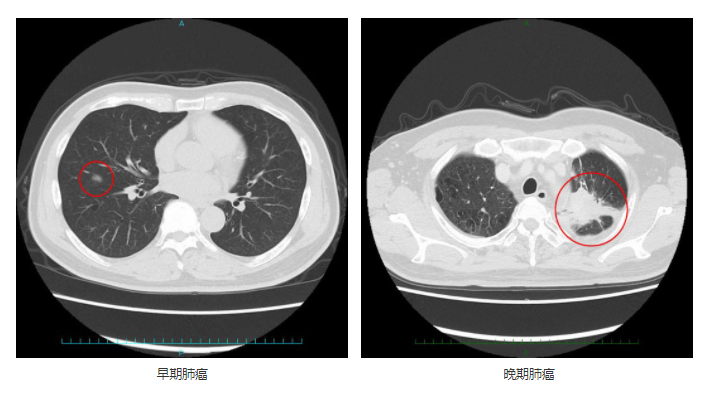

晚期非小細(xì)胞肺癌的免疫治療在2015年被美國(guó)FDA正式批準(zhǔn)為二線治療方案,到現(xiàn)在NCCN (美國(guó)國(guó)立綜合癌癥網(wǎng))指南建議 Pembrolizumab (帕博利珠單抗)用于 PD?L1 高表達(dá)的非小細(xì)胞肺癌的一線治療,ICI(免疫檢查點(diǎn)抑制劑)正式成為肺癌的一線藥物。非小細(xì)胞肺癌的一線二線免疫治療方案變得更加豐富,其中包括單藥使用和聯(lián)合給藥多種方案的治療。對(duì)于肺癌晚期來(lái)說(shuō),目前肺癌的免疫治療主要是免疫檢查點(diǎn)抑制劑,那么免疫治療藥物的效果到底如何?